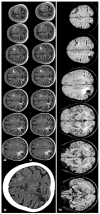

Spontaneous convexity subarachnoid hemorrhage (cSAH) is a vascular disease different from aneurysmal SAH in neuroimaging pattern, causes, and prognosis. Several causes might be considered in individual patients, with a limited value of the patient's age for discriminating among these causes. Cerebral amyloid angiopathy (CAA) is the most prevalent cause in people > 60 years, but reversible cerebral vasoconstriction syndrome (RCVS) has to be considered in young people. CAA gained attention in the last years, but the most known manifestation of cSAH in this context is constituted by transient focal neurological episodes (TFNEs). CAA might have an inflammatory side (CAA-related inflammation), whose diagnosis is relevant due to the efficacy of immunosuppression in resolving essudation. Other causes are hemodynamic stenosis or occlusion in extracranial and intracranial arteries, infective endocarditis (with or without intracranial infectious aneurysms), primary central nervous system angiitis, cerebral venous thrombosis, and rarer diseases. The diagnostic work-up is fundamental for an etiological diagnosis and includes neuroimaging techniques, nuclear medicine techniques, and lumbar puncture. The correct diagnosis is the first step for choosing the most effective and appropriate treatment.